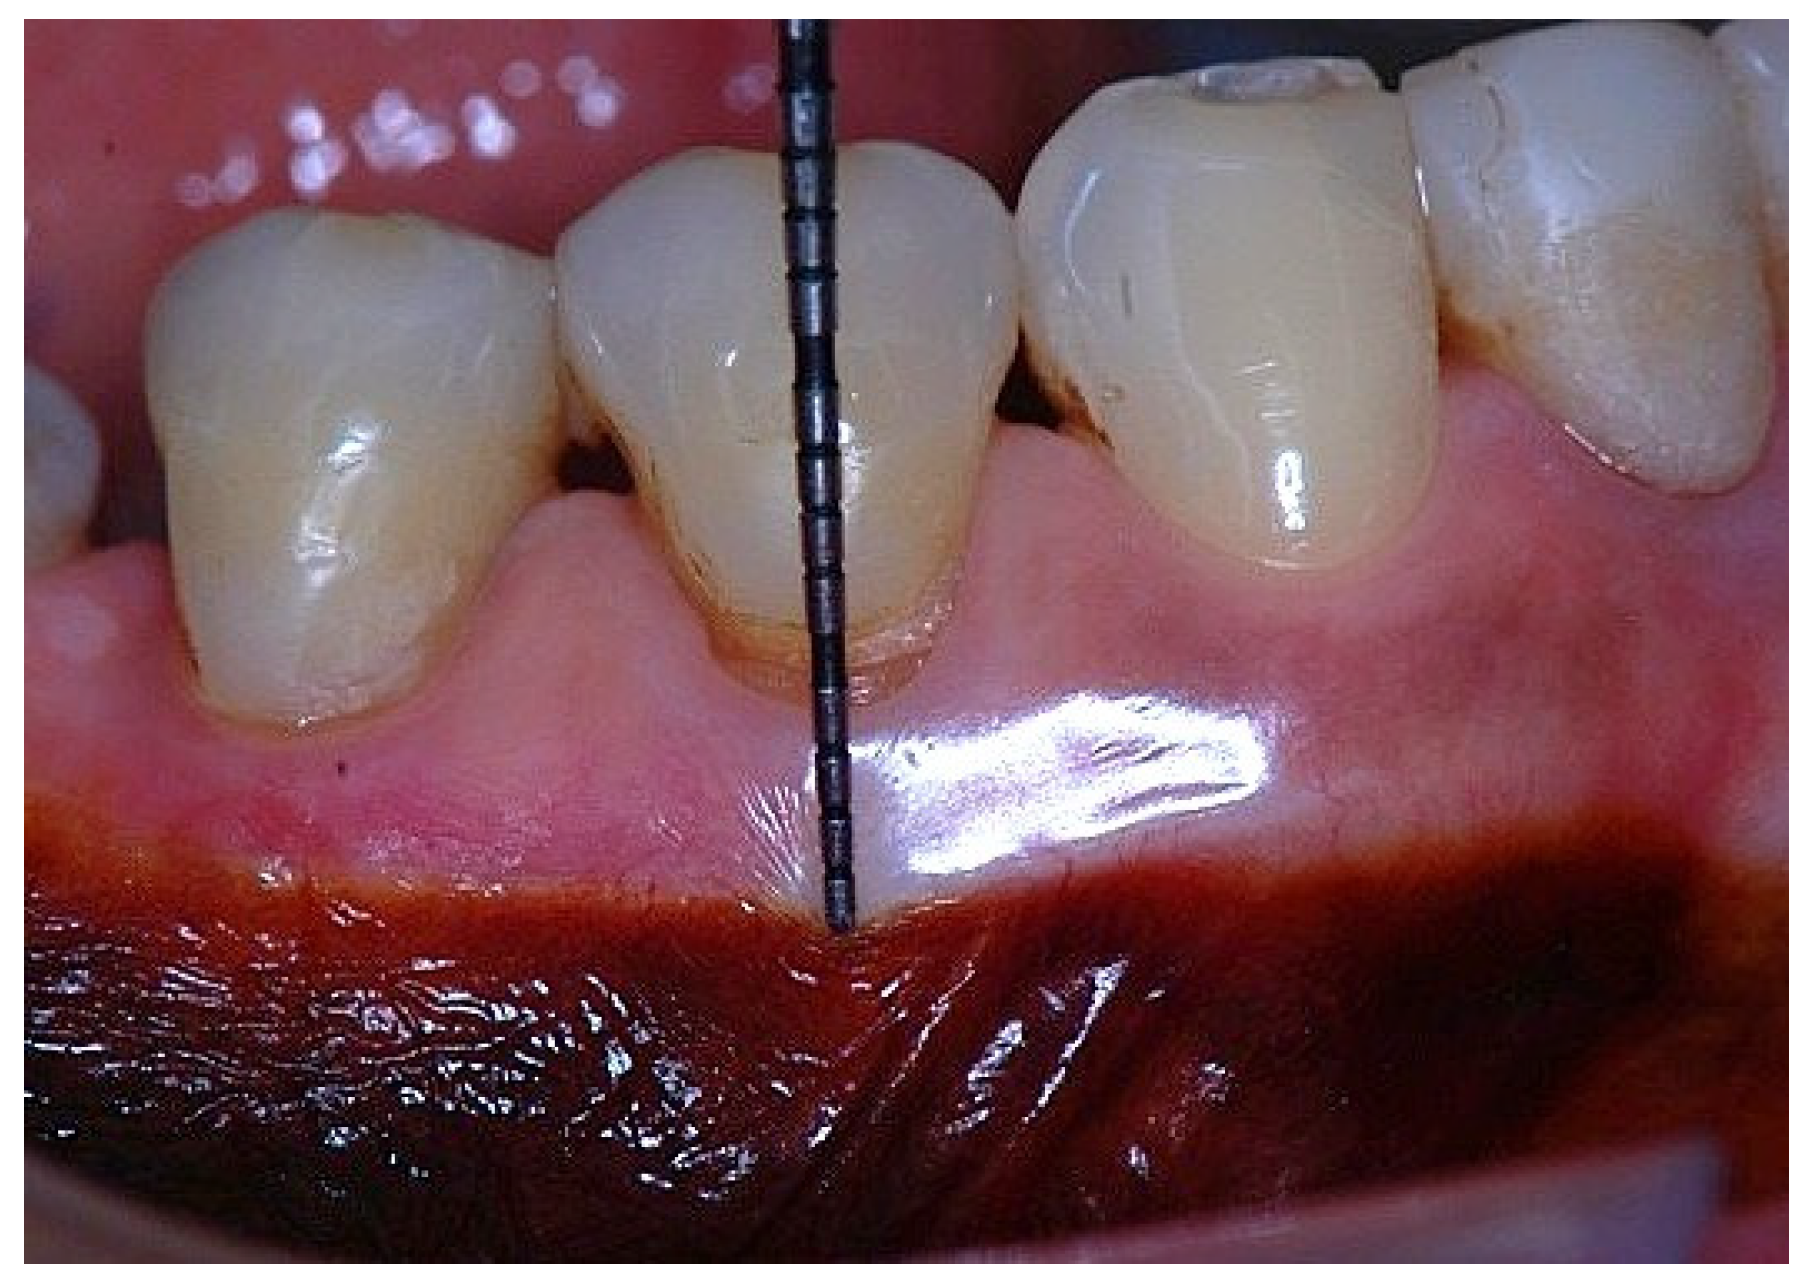

Figure 1. Probing depth of 1 mm is associated with approximately 1 mm of epithelial attachment.

In a clinical scenario characterized by 2 mm of keratinized tissue and a sulcus depth of 1 mm, a stable and mechanically resistant connective tissue attachment is not present [1]. This is attributable to the fact that most connective tissue fibers inserting into the root surface are associated with non-keratinized, mobile mucosal tissues (Figure 1), which are elastic in nature and therefore incapable of stabilizing the gingival margin (Figure 2 and Figure 3). In contrast, when these fibers are embedded within keratinized tissue, they are firmly anchored to both the tooth and alveolar bone and are comparatively immobile, thereby contributing to gingival margin stability (Figure 4, Figure 5 and Figure 6).

Clinically, the buccal and lingual width of AG is estimated by subtracting the sulcus or pocket depth from the distance between the gingival margin and the mucogingival junction. This method inherently includes the junctional epithelium within the clinical measurement of AG, despite the distinct structural and functional characteristics of epithelial and connective tissue attachments [2]. Consequently, the proportion of JE included in this measurement may vary depending on probing depth and inflammatory status. Recognition of these distinctions is essential when interpreting the functional significance of AG in periodontal stability [7].